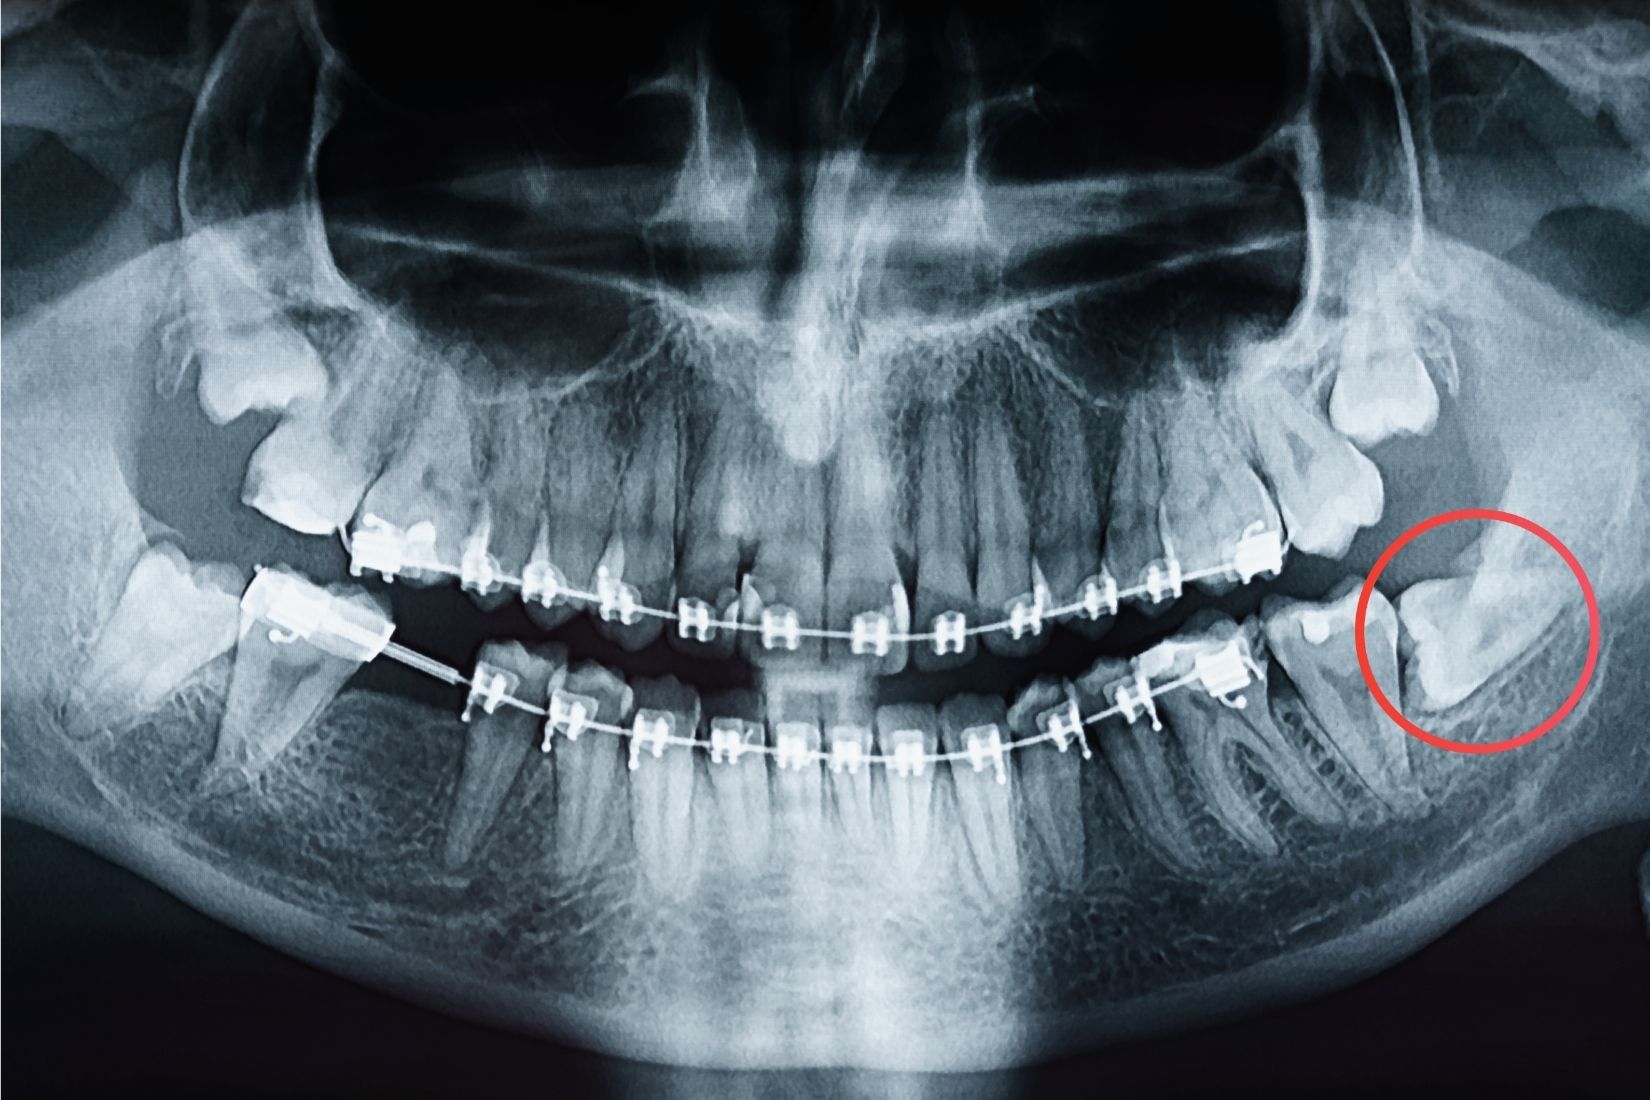

Konya gömülü diş tedavisi planlanırken ilk basamak ayrıntılı muayenedir. Muayenede diş eti durumu, şişlik, hassasiyet, kısmi sürme olup olmadığı, komşu dişlerin etkilenip etkilenmediği ve ağız hijyeni değerlendirilir. Bunun ardından panoramik röntgen ve gerekli görülen olgularda daha ileri görüntüleme yöntemleri kullanılabilir. Bu incelemelerle dişin konumu, kök gelişimi, kemikle ilişkisi ve çevre anatomik yapılarla komşuluğu incelenir.

Özellikle gömülü kanin dişlerde, dişin uygun konuma getirilebilme ihtimali varsa cerrahi olarak açığa çıkarma ve ortodontik yönlendirme planlanabilir. Bu yaklaşım her vaka için uygun değildir; dişin yönü, yaşı, kök gelişimi ve çevre yapıların durumu birlikte değerlendirilir. Bu nedenle Konya gömülü diş tedavisi bazı hastalarda ortodonti ile birlikte planlanabilir. Bu çıkarım, gömülü dişlerin ön bölgede yer alması halinde dişin uygun konuma braces ile getirilebildiğini belirten hasta bilgilendirme kaynaklarıyla uyumludur.

- Gömülü diş tanısı klinik muayene ve radyografik incelemeler ile konur. Panoramik röntgen ve gerekli görülen durumlarda üç boyutlu görüntüleme yöntemleri ile dişin konumu, yönü ve çevre anatomik yapılarla ilişkisi değerlendirilir.